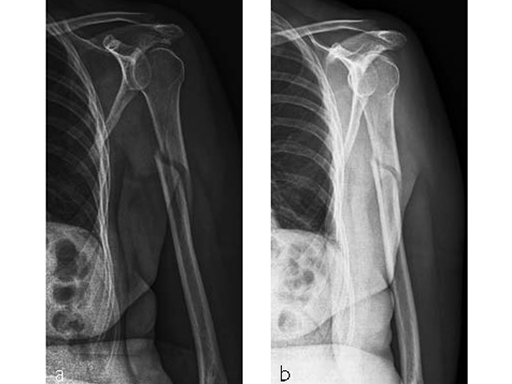

Case 1: A three-part valgus impacted fracture of the proximal humerus in a 47-year-old woman.

Case provided by Stefaan Nijs, Leuven, Belgium